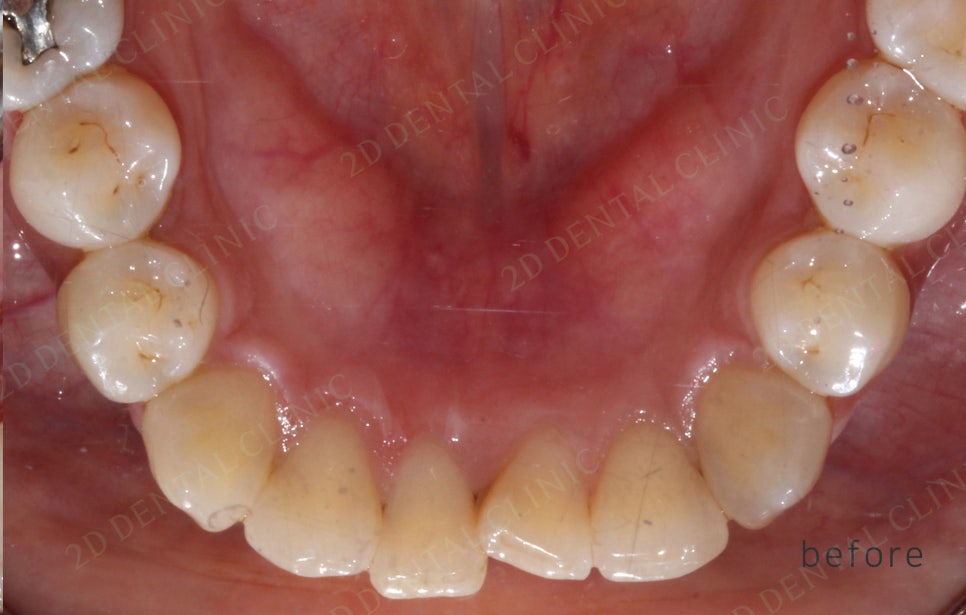

<교정 전/후 >

2D(투디)교정 앞니덧니,반대교합 치아교정

191일(약 6개월)후 투디교정 완료.

전,후 사진만 봐도 치아 배열이 잘

정돈된게 보이시나요!?